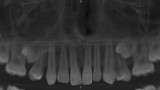

Resorpcja zęba to proces powstania ubytku twardych struktur zęba wywołanego przez osteoklasty bez kontaktu ze środowiskiem jamy ustnej, między innymi na skutek ucisku wywieranego przez ząb zatrzymany. Dla lekarza ortodonty jest istotne ustalenie, czy zęby zatrzymane lub twory nadliczbowe powodują resorpcję zębów stojących w łuku w celu wczesnej eliminacji przyczyny resorpcji. Celem pracy jest przedstawienie opisu przypadku zastosowania tomografii stożkowej w diagnostyce nieprawidłowo położonych zawiązków zębów przedtrzonowych drugich górnych. Stwierdzono, że tomografia stożkowa jest skuteczną metodą oceny wczesnej resorpcji zewnętrznej korzeni zębów.

Tooth resorption is the process of appearing of a defect of hard tissues of teeth caused by osteoclasts not having contact with oral cavity environment, eg. due to mechanical pressure exerted by an impacted tooth. It is essential for an orthodontist whether impacted teeth or supplementary teeth cause resorption of erupted teeth in order to early eliminate the causative factor of the resorption. The aim of the paper is to describe a case report of cone-beam computed tomography (CBCT) in diagnostics of incorrectly located germs of upper second premolars. It was found that CBCT was an efficient method of imaging of early external root resorption.